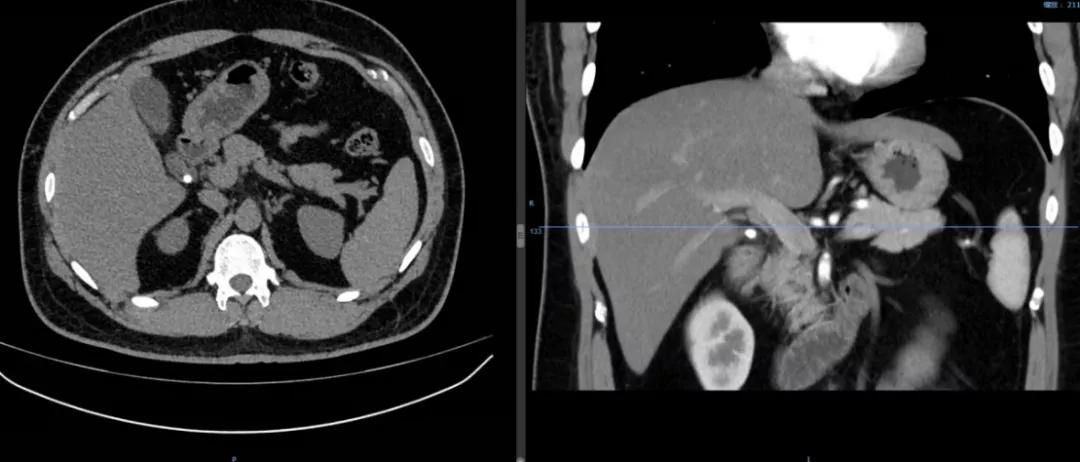

案例四

47岁男性,胆囊结石多年,未予重视。与朋友聚餐后突发腹痛并身目黄染急诊入院,检查提示胆囊最大结石直径超过4cm,胆总管下端小结石堵塞致肝内外胆管扩张,总胆红素超过300μmol/L(正常值为小于21μmol/L),行“腹腔镜胆囊切除+胆总管切开探查取石+T管引流”,术后症状缓解,黄疸逐步消退。